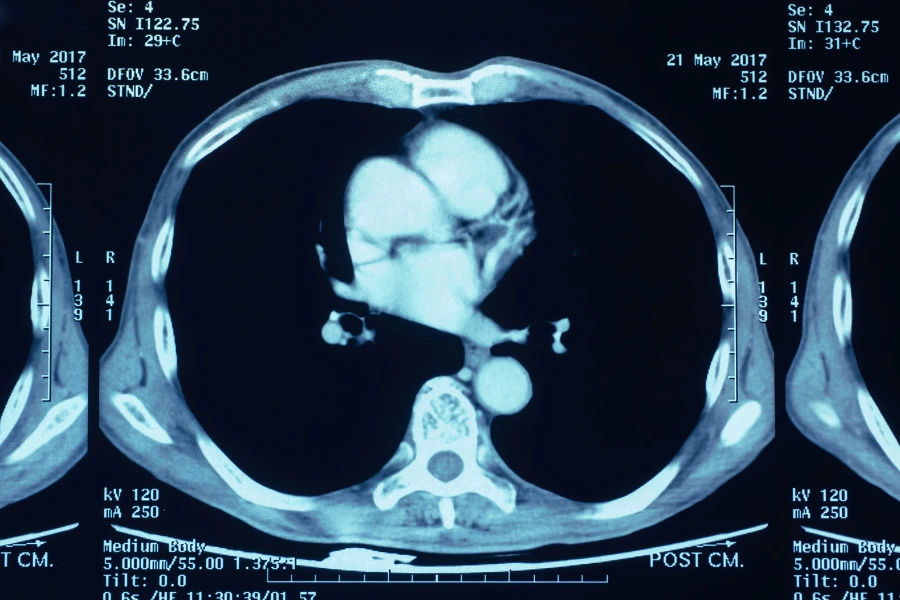

Особое место в онкологической практике занимает КТ трёх зон с контрастом — грудной клетки, брюшной полости и малого таза. Это комплексное исследование позволяет за одно сканирование оценить распространение опухолевого процесса, выявить метастазы и точно определить стадию заболевания. Такой формат диагностики часто используется при первичном выявлении рака, перед началом лечения, а также для контроля эффективности химио- или лучевой терапии.

Перед процедурой снимаются все металлические предметы — украшения, часы, ремни, аксессуары. Затем пациент размещается на выдвижном столе томографа, который медленно заезжает внутрь кольцевого сканера. Медсестра устанавливает внутривенный катетер для введения контраста. В момент введения возможно ощущение лёгкого тепла или металлического привкуса во рту — это нормальная реакция организма, которая проходит через несколько минут.

Само исследование длится примерно 10–20 минут. Важно сохранять неподвижность, поскольку даже небольшие движения могут снизить качество снимков. Связь с врачом поддерживается через микрофон — специалист даёт короткие команды, например, задержать дыхание.